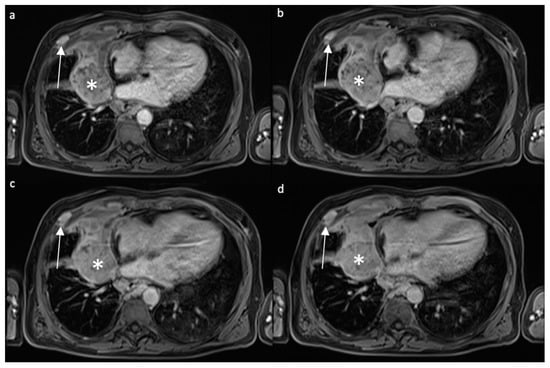

4.2.2. Contrast Enhancement-MRI

4.2.3. Diffusion-Weighted Imaging and Apparent Diffusion Coefficient